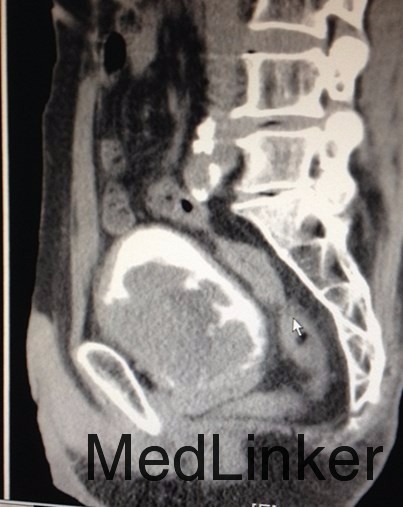

主诉:前列腺癌术后10月余,反复肉眼血尿6月 病史:老年男性,10月余前因进行性排尿困难到当地医院就诊,拟诊为前列腺增生,行TURP,术后病理提示前列腺组织内见高级别尿路上皮癌浸润,后予双侧睾丸切除术去势治疗,术后恢复良好出院。6月前患者无明显诱因反复出现全程肉眼血尿,淡红色,并伴尿痛、排尿困难,未见血块,无伴畏寒发热,无腹痛腰痛等不适。当地医院就诊,诊断“尿道结石”,予行尿道结石钳出+膀胱镜检+尿道扩张术。出院后患者仍反复血尿,性质同前。遂至我院门诊就诊,行腹部CT见:膀胱肿瘤。收入院治疗。

查体:右侧腋窝及右侧锁骨上可触及淋巴结肿大,质硬,移动度差。双侧睾丸缺如。 辅助检查:我院CTU提示膀胱癌,侵犯前列腺及左侧输尿管下段,可疑侵犯右侧精囊腺。